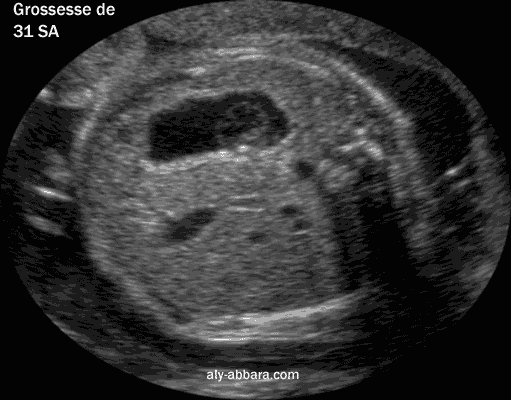

Image échographique montrant l'estomac foetal avec son contenu prenant la forme d'un pseudokyste et disparaissant 10 minutes plus tard

Coupe échographique transversale abdominale montrant l'estomac fœtal avec son contenu prenant la forme d'un pseudokyste et disparaissant 10 minutes plus tard

fœtus âgé de 31SA.